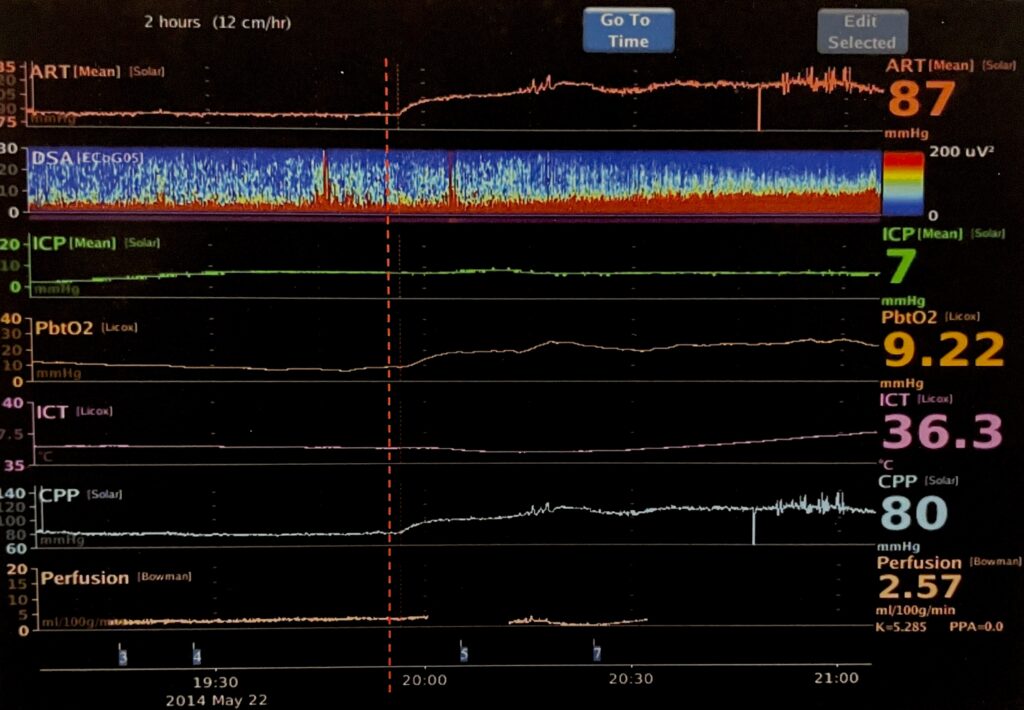

Moberg Analytics CNS Monitor Synchronized Data

Synchronized data shows the action of a vasopressor (given at red line) on other trends.